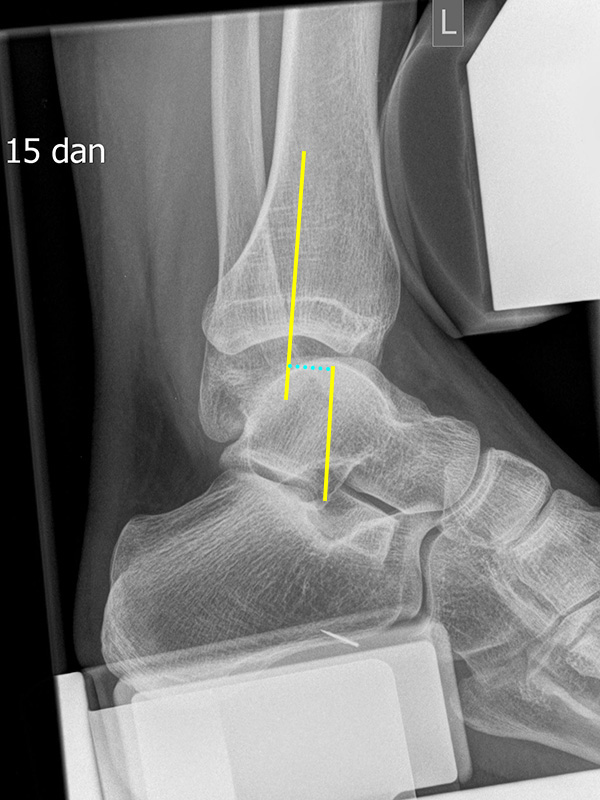

Stressaufnahme des oberen Sprunggelenks lateral

Position:

• Patient in Seitenlage auf dem Röntgentisch, zu untersuchender Fuß unten und seitlich auf der Röntgenkassette liegend (Achse des Fußes parallel zum Zentralstrahl).

• Zentralstrahl mittig auf das obere Sprunggelenk fokussiert.

• Film horizontal auf dem Röntgentisch.

• Röntgenröhre 0° vertikal.

• Der Fuß liegt in der Haltevorrichtung (z.B. Telos-Gerät, Scheuba-Apparat). Die Ferse wird von dorsal stabilisiert.

• Von ventral wird über die Tibia ein kontrollierter Druck von bis zu 15 daN (Dekanewton, entspricht ca. 15 kg) aufgebaut.

Kennzeichen des Röntgenbildes:

• Laterale Abbildung des oberen Sprunggelenks.

• Beurteilung der Translokation des Talus nach ventral (Talusvorschub).

• Gemessen wird die Verschiebung der Tibiaachse gegenüber der Talusachse.

• Als pathologisch gelten Talusvorschub > 2 mm im Seitenvergleich oder absoluter Talusvorschub > 4 mm.

Besondere Bemerkungen zum Beispielbild:

• Abbildung des oberen Sprunggelenks lateral.

• Fremdkörper in den plantaren Weichteilen in Höhe der plantaren Begrenzung des Kalkaneus.